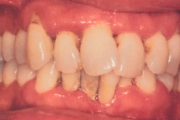

Krooniline parodontiit

Krooniline parodontiit on mikroobide poolt põhjustatud hammaste tugikudede põletik, mille tulemusena tekib progresseeruv alveolaarluu (nähtav röntgenograamil) ja periodontaalligamendi destruktsioon, igemetaskute moodustumine, igeme retsessioon või mõlemad kahjustused kombineeritult. Loe edasi »

- igemepiir on taandunud (3)

- hamba kinnitussidemete kadu (3)